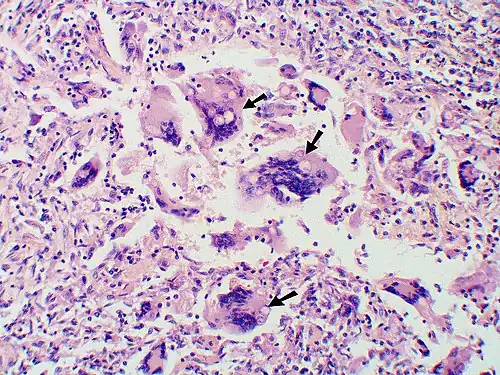

Large yeast-like fungi seen within giant cells at arrows. -

Large yeast-like fungi seen within giant cells at arrows. Budding yeasts in the cytoplasm of giant cells at the arrows. Broad-based budding and double-contoured cell walls are seen in the giant cell in the center are characteristic of Blastomyces dermatitidis. -